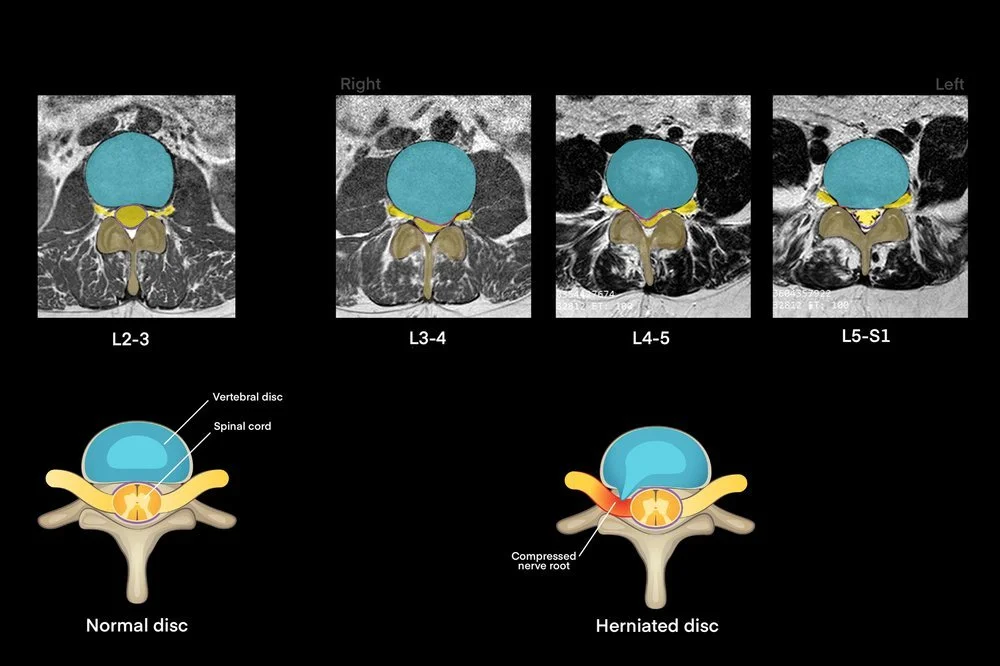

Colorization of axial MRI showing herniation with graphic examples of healthy and injured vertebral discs